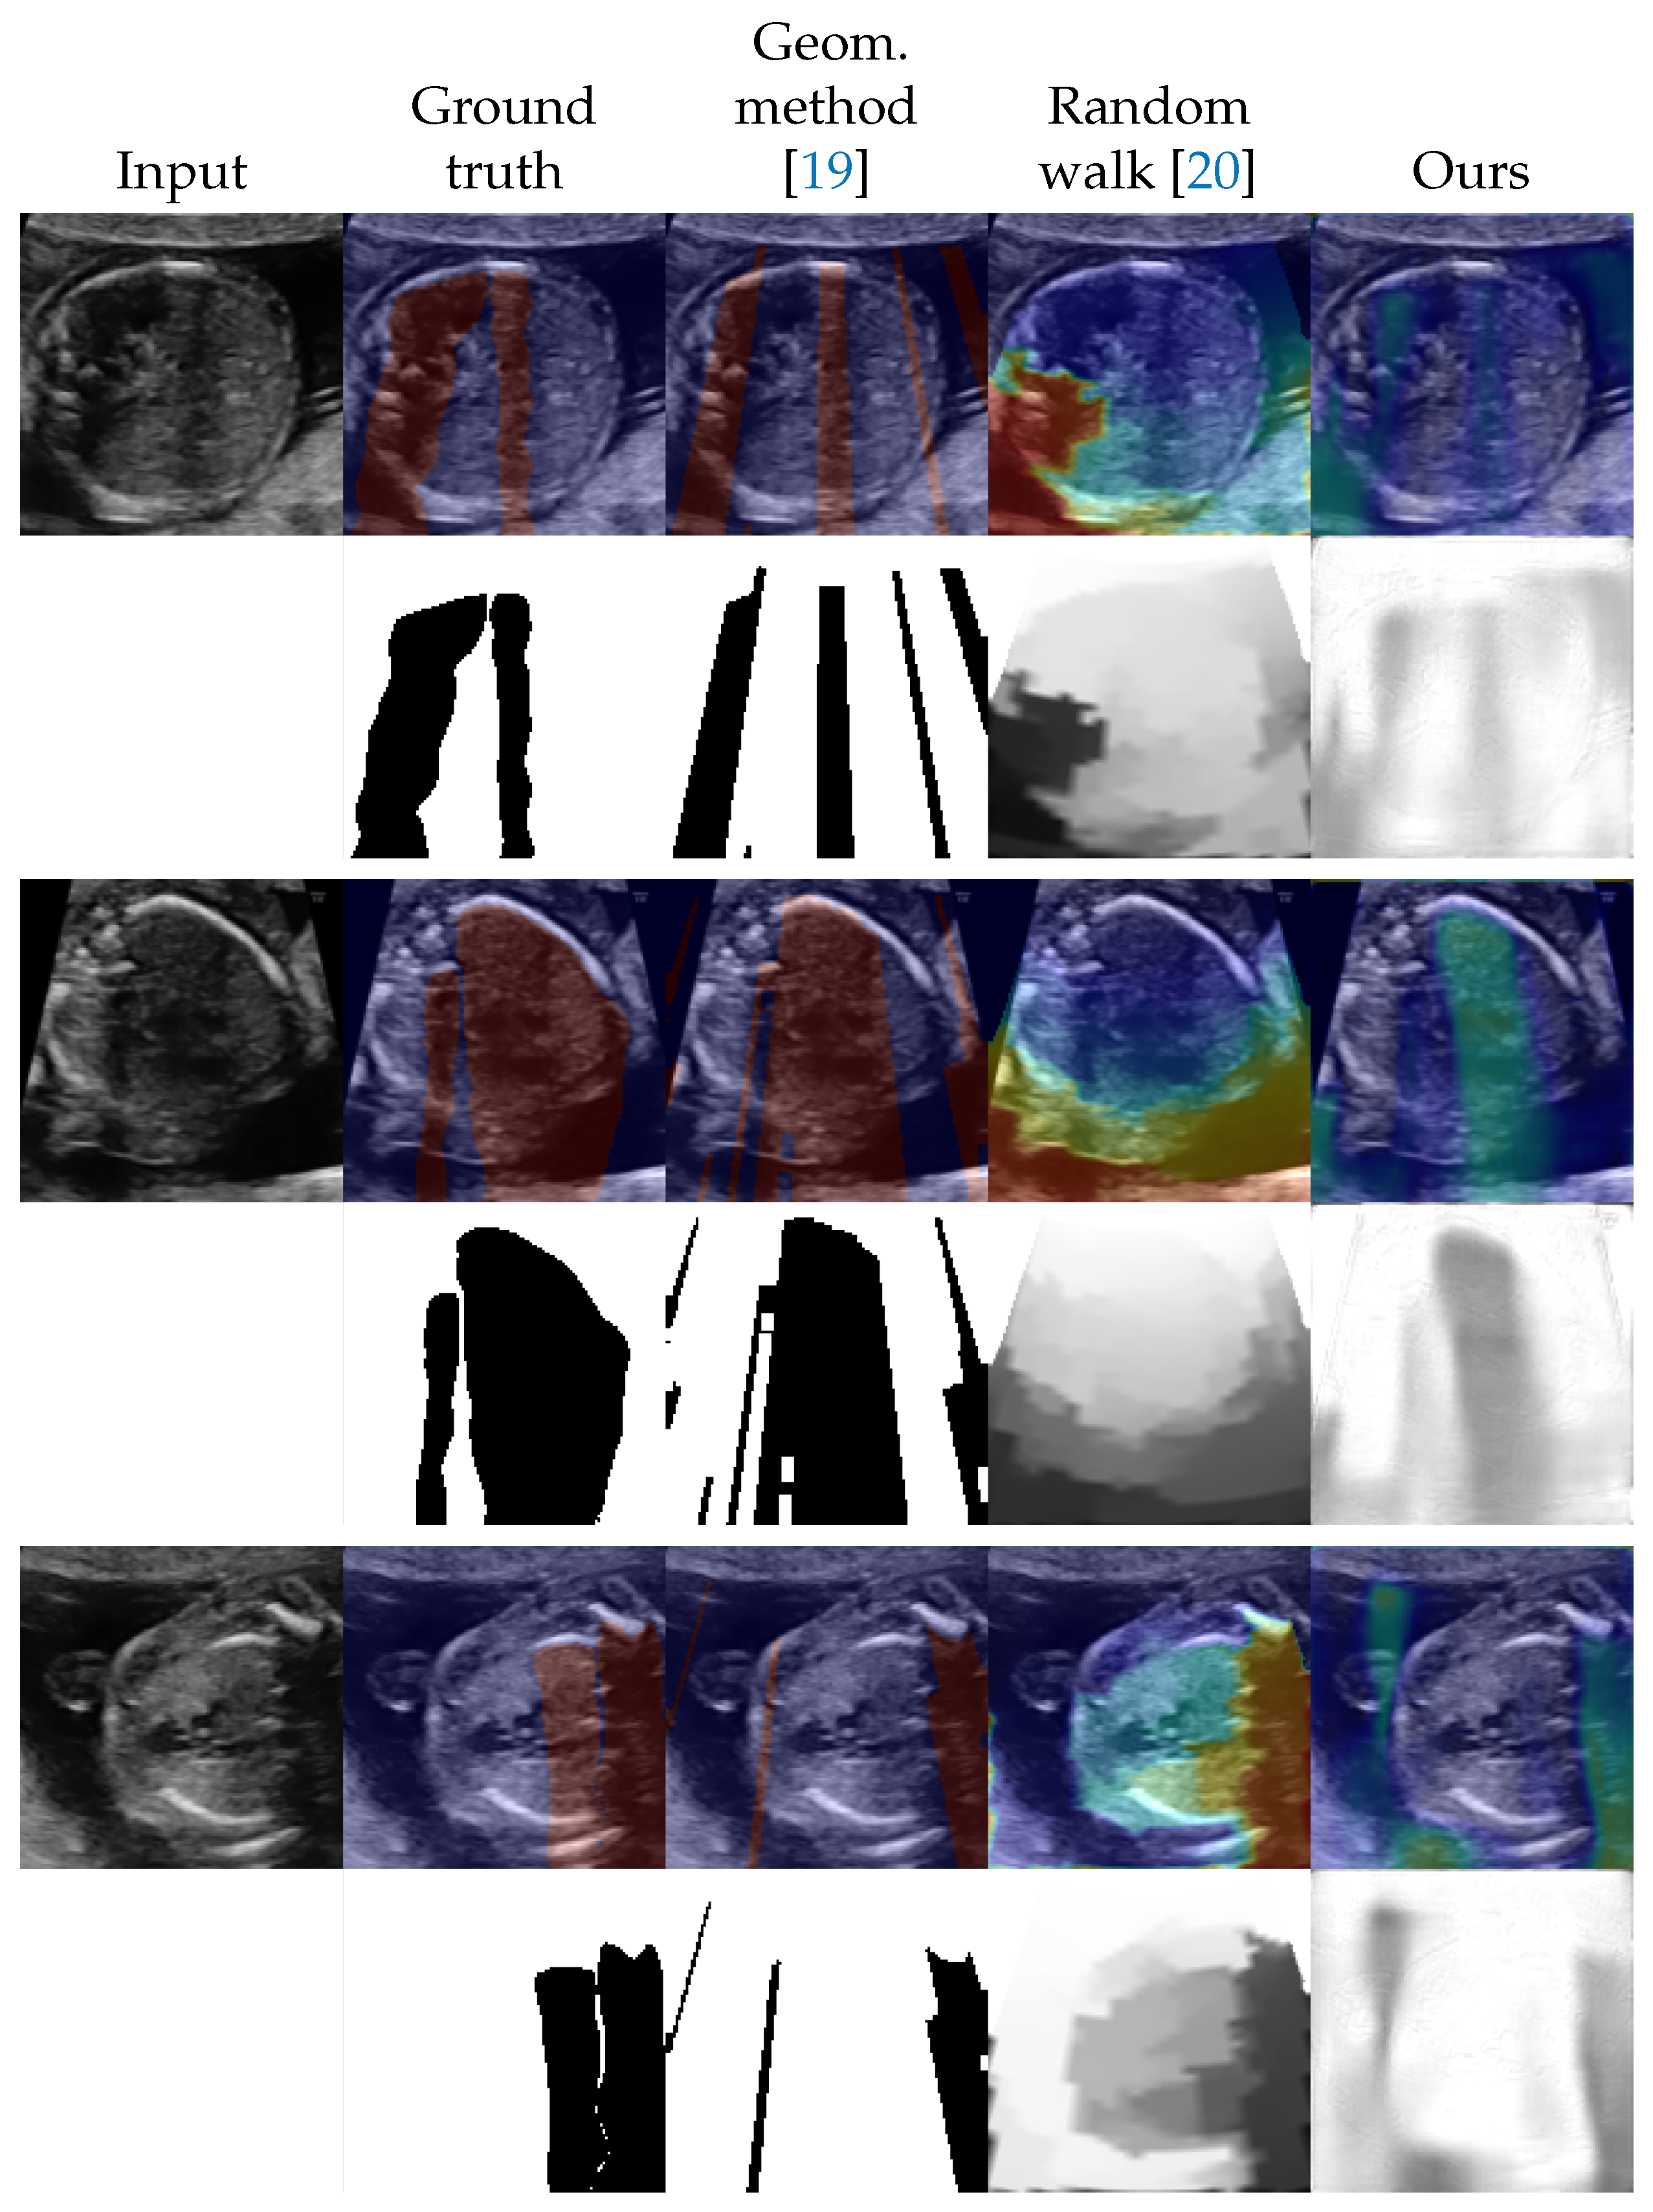

4.2. Shadow Detection

4.3. Shadow Intensity Estimation